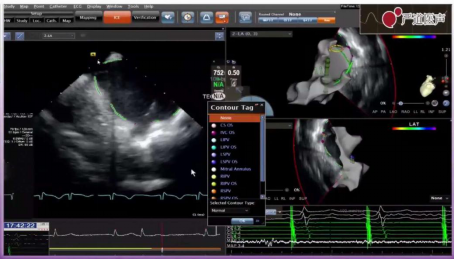

手术由张培教授完成,患者为69岁男性,诊断持续性房颤、I度房室传导阻滞,采用UPS术式,全程零射线,并且结合了可视可调弯鞘进行全程手术。选择右侧股静脉穿刺,确认左心耳无血栓后,利用超声进行左房建模,进行肺静脉隔离。采用单房间隔穿刺,进行两个圈隔离,术前房颤容易诱发,隔离后心房反复诱发,未发作房颤。电压标测后壁电压正常,前壁电压偏低,考虑为主动脉切迹引起,但现在无法定论。患者消融过程顺利,消融效果良好。

消融前电压标测

房间隔穿刺